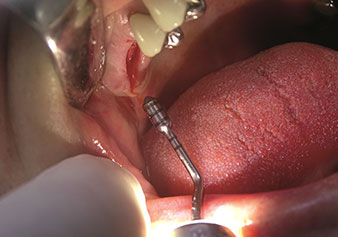

W&H bietet auch die perfekte Lösung für den internen Sinuslift an Nach der Kieferhöhlenpräparation mit dem

entsprechenden Instrumentarium (Abb. 3) erfolgt mit dem neuen Instrument Z35P (Abb. 4) die hydrodynamische Abhebung der Membran. Mit dem gleichen Instrumentenset kann auch die Implantatbett-Aufbereitung piezochirurgisch in aufsteigenden Durchmessern erfolgen (Abbildung drei und vier mit freundlicher Genehmigung von Dr. Mario Kirste, Frankfurt/Oder).